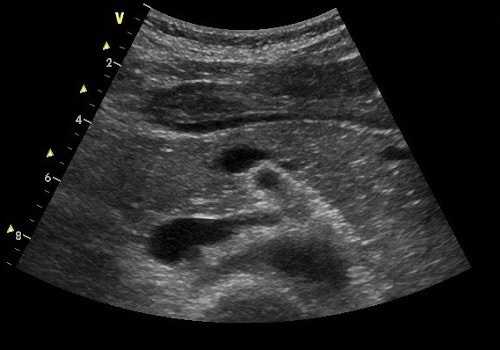

К скриннинговым методам относится ультразвуковое исследование (УЗИ), получившее положительный отзыв врачей разных специальностей. Сонография удобна тем, что не требует сложной подготовки, занимает мало времени, ее хорошо переносит и ребёнок, и человек пожилого возраста. С помощью этой методики определяются:

- размеры,

- наличие образований,

- четкость границ,

- эхогенность (плотность) тканей — повышенная или сниженная,

- состояние вирсунгова протока.

При проведении сонографии в некоторых случаях не лоцируется хвост измененной поджелудочной железы. Он может визуализироваться частично и непостоянно. По данным литературы, частота обнаружения хвоста ПЖ на эхографии составляет приблизительно 40-100%. Лучше удается лоцировать значительно увеличенную хвостовую часть органа, особенно при имеющихся в ней эхопозитивных образованиях больших размеров.